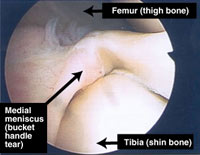

Bucket Handle Tear Normal

This can cause severe damage to the meniscii either wrenching them from their attachment ("peripheral detachment") or by splitting off a large "bucket handle" segment. This is different to the common degenerative tear where a meniscus has gradually become weaker and weaker to finally fail following a trivial injury ("the straw that broke the Camel's back").